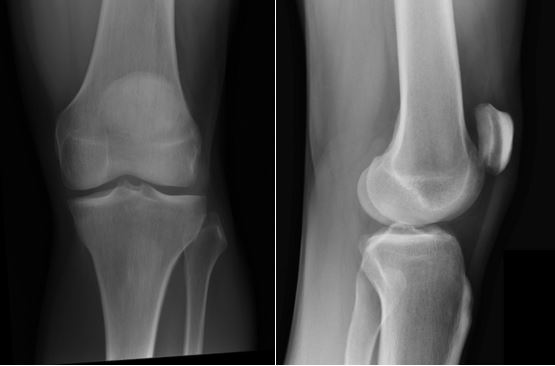

This is a normal knee X-ray as would be expected with PFS

Case courtesy of Dr Andrew Dixon, Radiopaedia.org. From the case rID: 36689